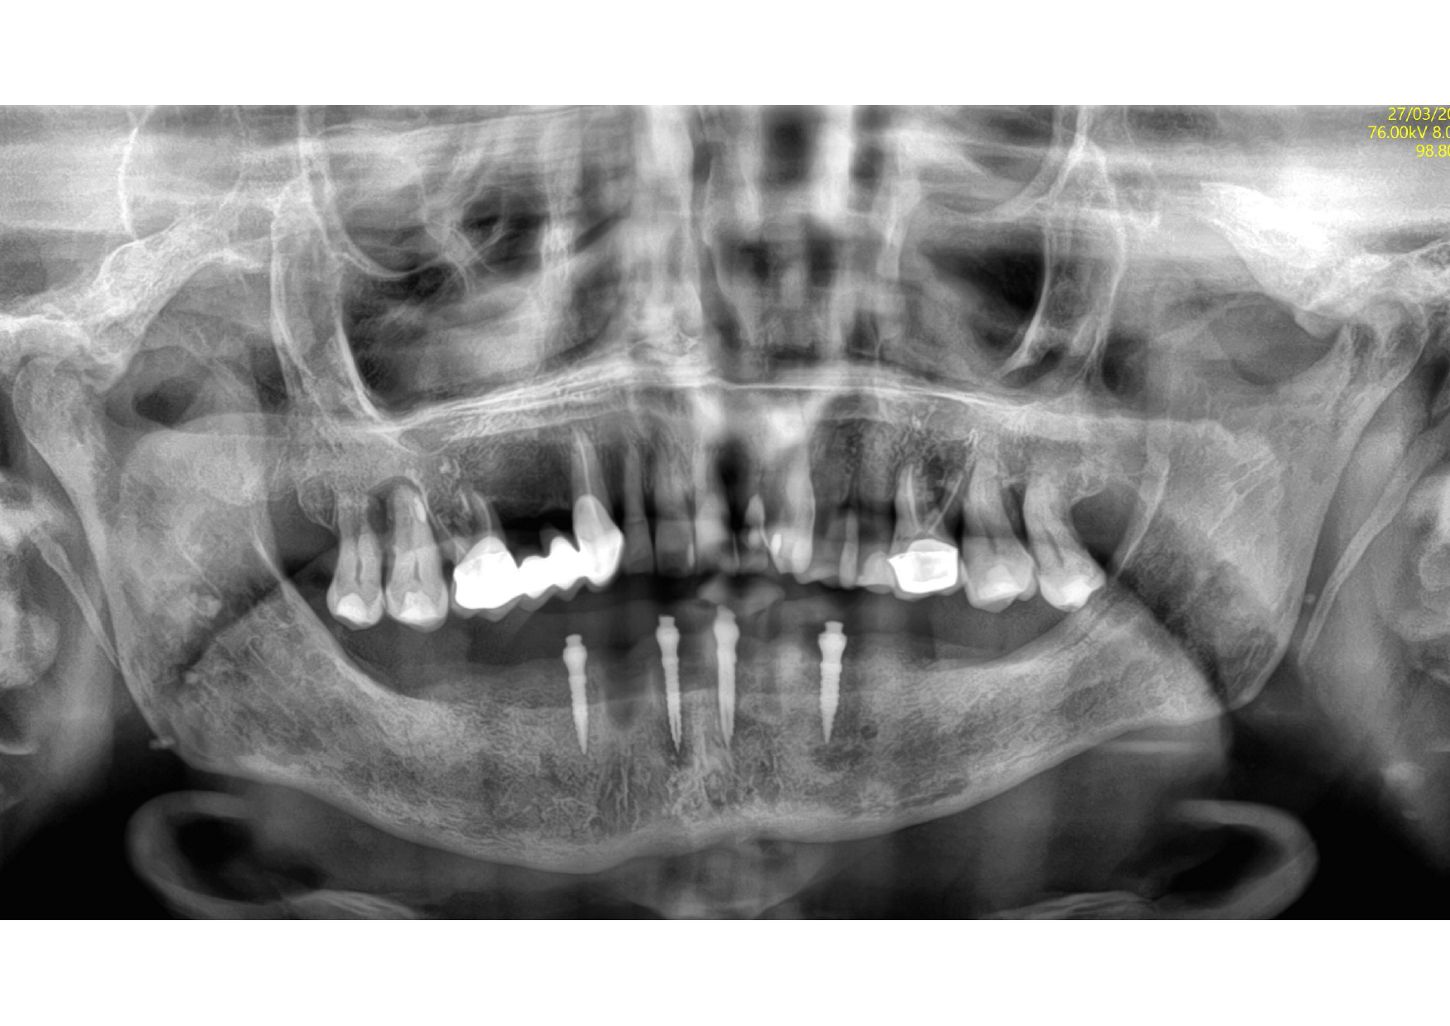

1a. 1b. Pre-operative panoramic X-ray and CBCT showing moderate generalised bone resorption in the mandible, a reduction in vertical dimension in the posterior region and the planned positioning of mini- implants.

1a

1b

6. Post-operative X-ray showing the implants in place as planned.

6